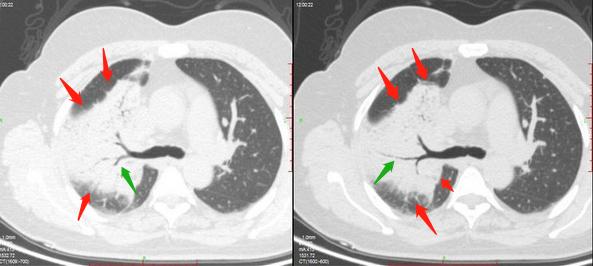

从老家过来的一位女病人,56岁,咳嗽胸闷4个月,CT发现右肺大片高密度影:

我们分析她的片子,右肺上叶大片实变(红箭头),里面可以看到管状的支气管(绿箭头),并且支气管走行僵直、扩张。

这个支气管改变很有价值!我们知道,肺炎的时候支气管是光滑自然的,

而这位病人的支气管发生了扩张,并且边缘轮廓不够光滑:

这就提示了两个疾病:肺粘液腺癌和肺淋巴瘤。